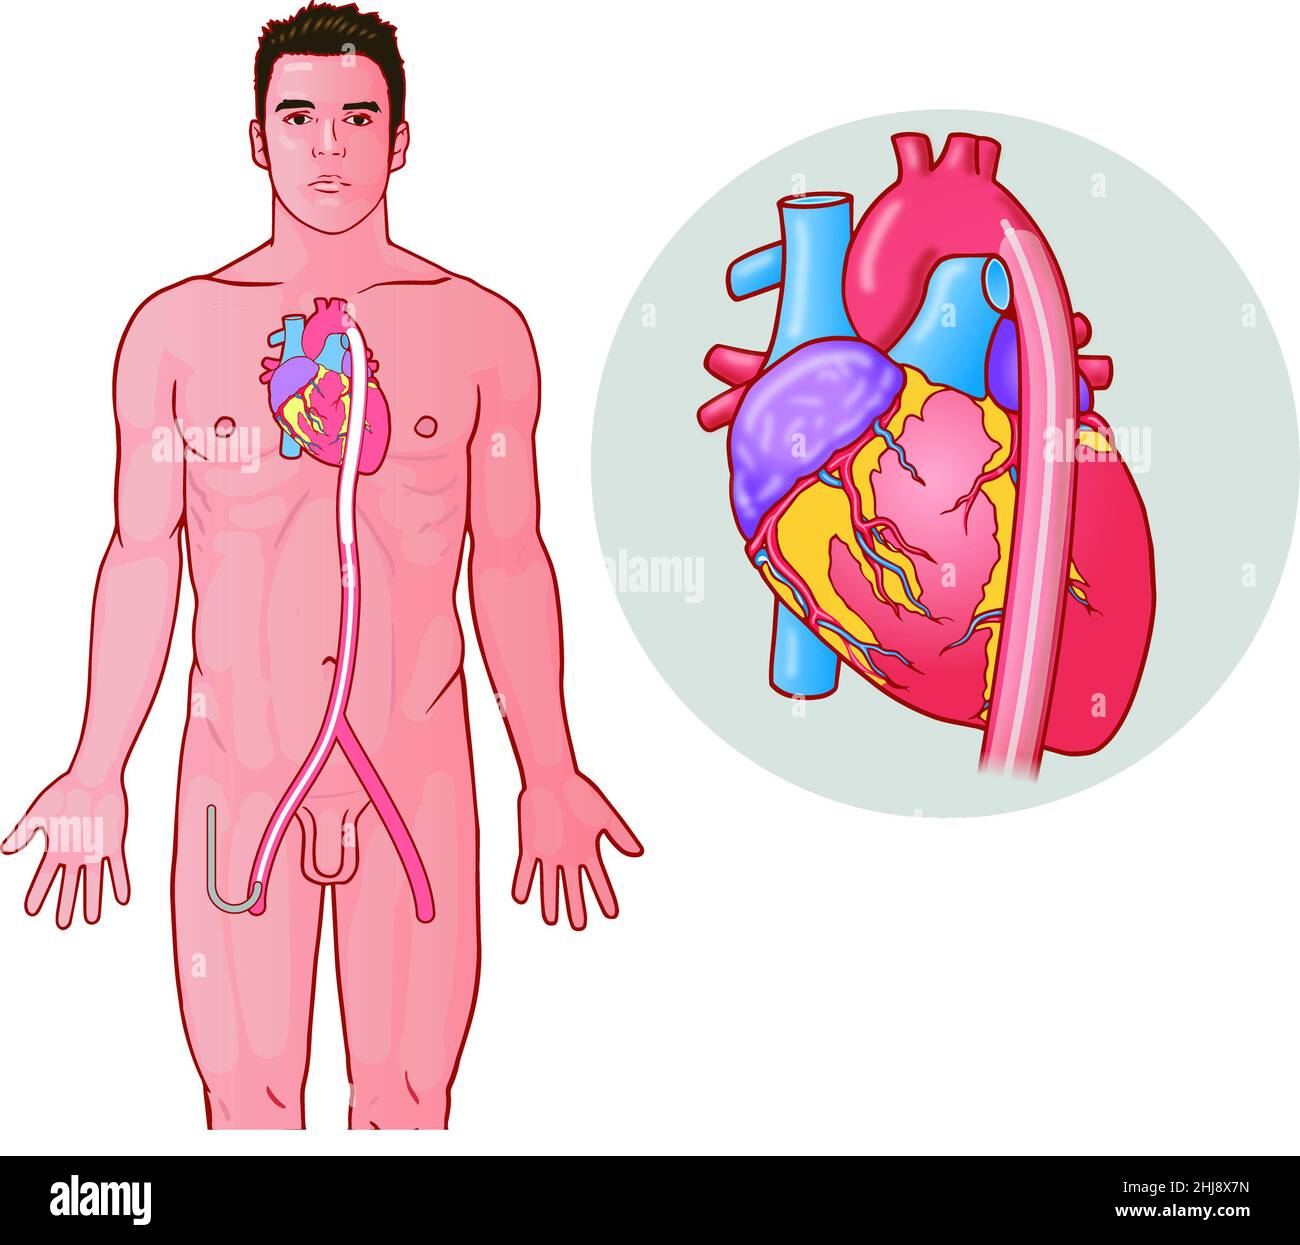

One of three in a series of medical art diagrams showing how an intra-aortic balloon pump (IABP) therapy device is attached Educational biology topics Stock Photohttps://www.alamy.com/image-license-details/?v=1https://www.alamy.com/one-of-three-in-a-series-of-medical-art-diagrams-showing-how-an-intra-aortic-balloon-pump-iabp-therapy-device-is-attached-educational-biology-topics-image458729593.html

One of three in a series of medical art diagrams showing how an intra-aortic balloon pump (IABP) therapy device is attached Educational biology topics Stock Photohttps://www.alamy.com/image-license-details/?v=1https://www.alamy.com/one-of-three-in-a-series-of-medical-art-diagrams-showing-how-an-intra-aortic-balloon-pump-iabp-therapy-device-is-attached-educational-biology-topics-image458729593.htmlRM2HJ8X7N–One of three in a series of medical art diagrams showing how an intra-aortic balloon pump (IABP) therapy device is attached Educational biology topics